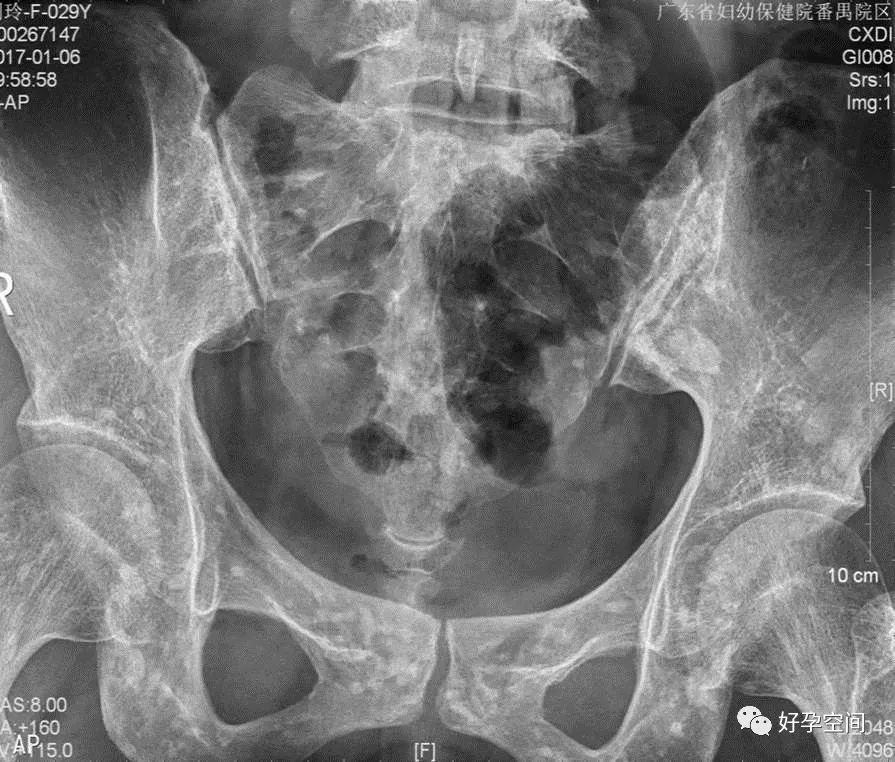

3、骨斑点症

骨盆诸骨均可见多发小圆形高密度影